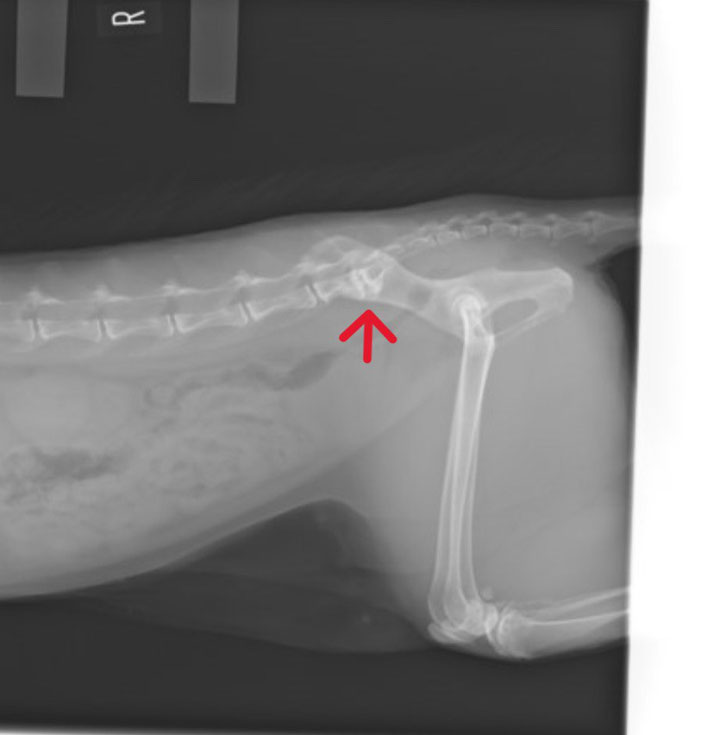

📷 レントゲンで見る馬尾症候群

上の写真は猫の腰から尾にかけてのレントゲン画像です。

赤い矢印の部分(腰の一番後ろの骨〜尾の付け根)で神経が圧迫されており、馬尾症候群が疑われる所見です。